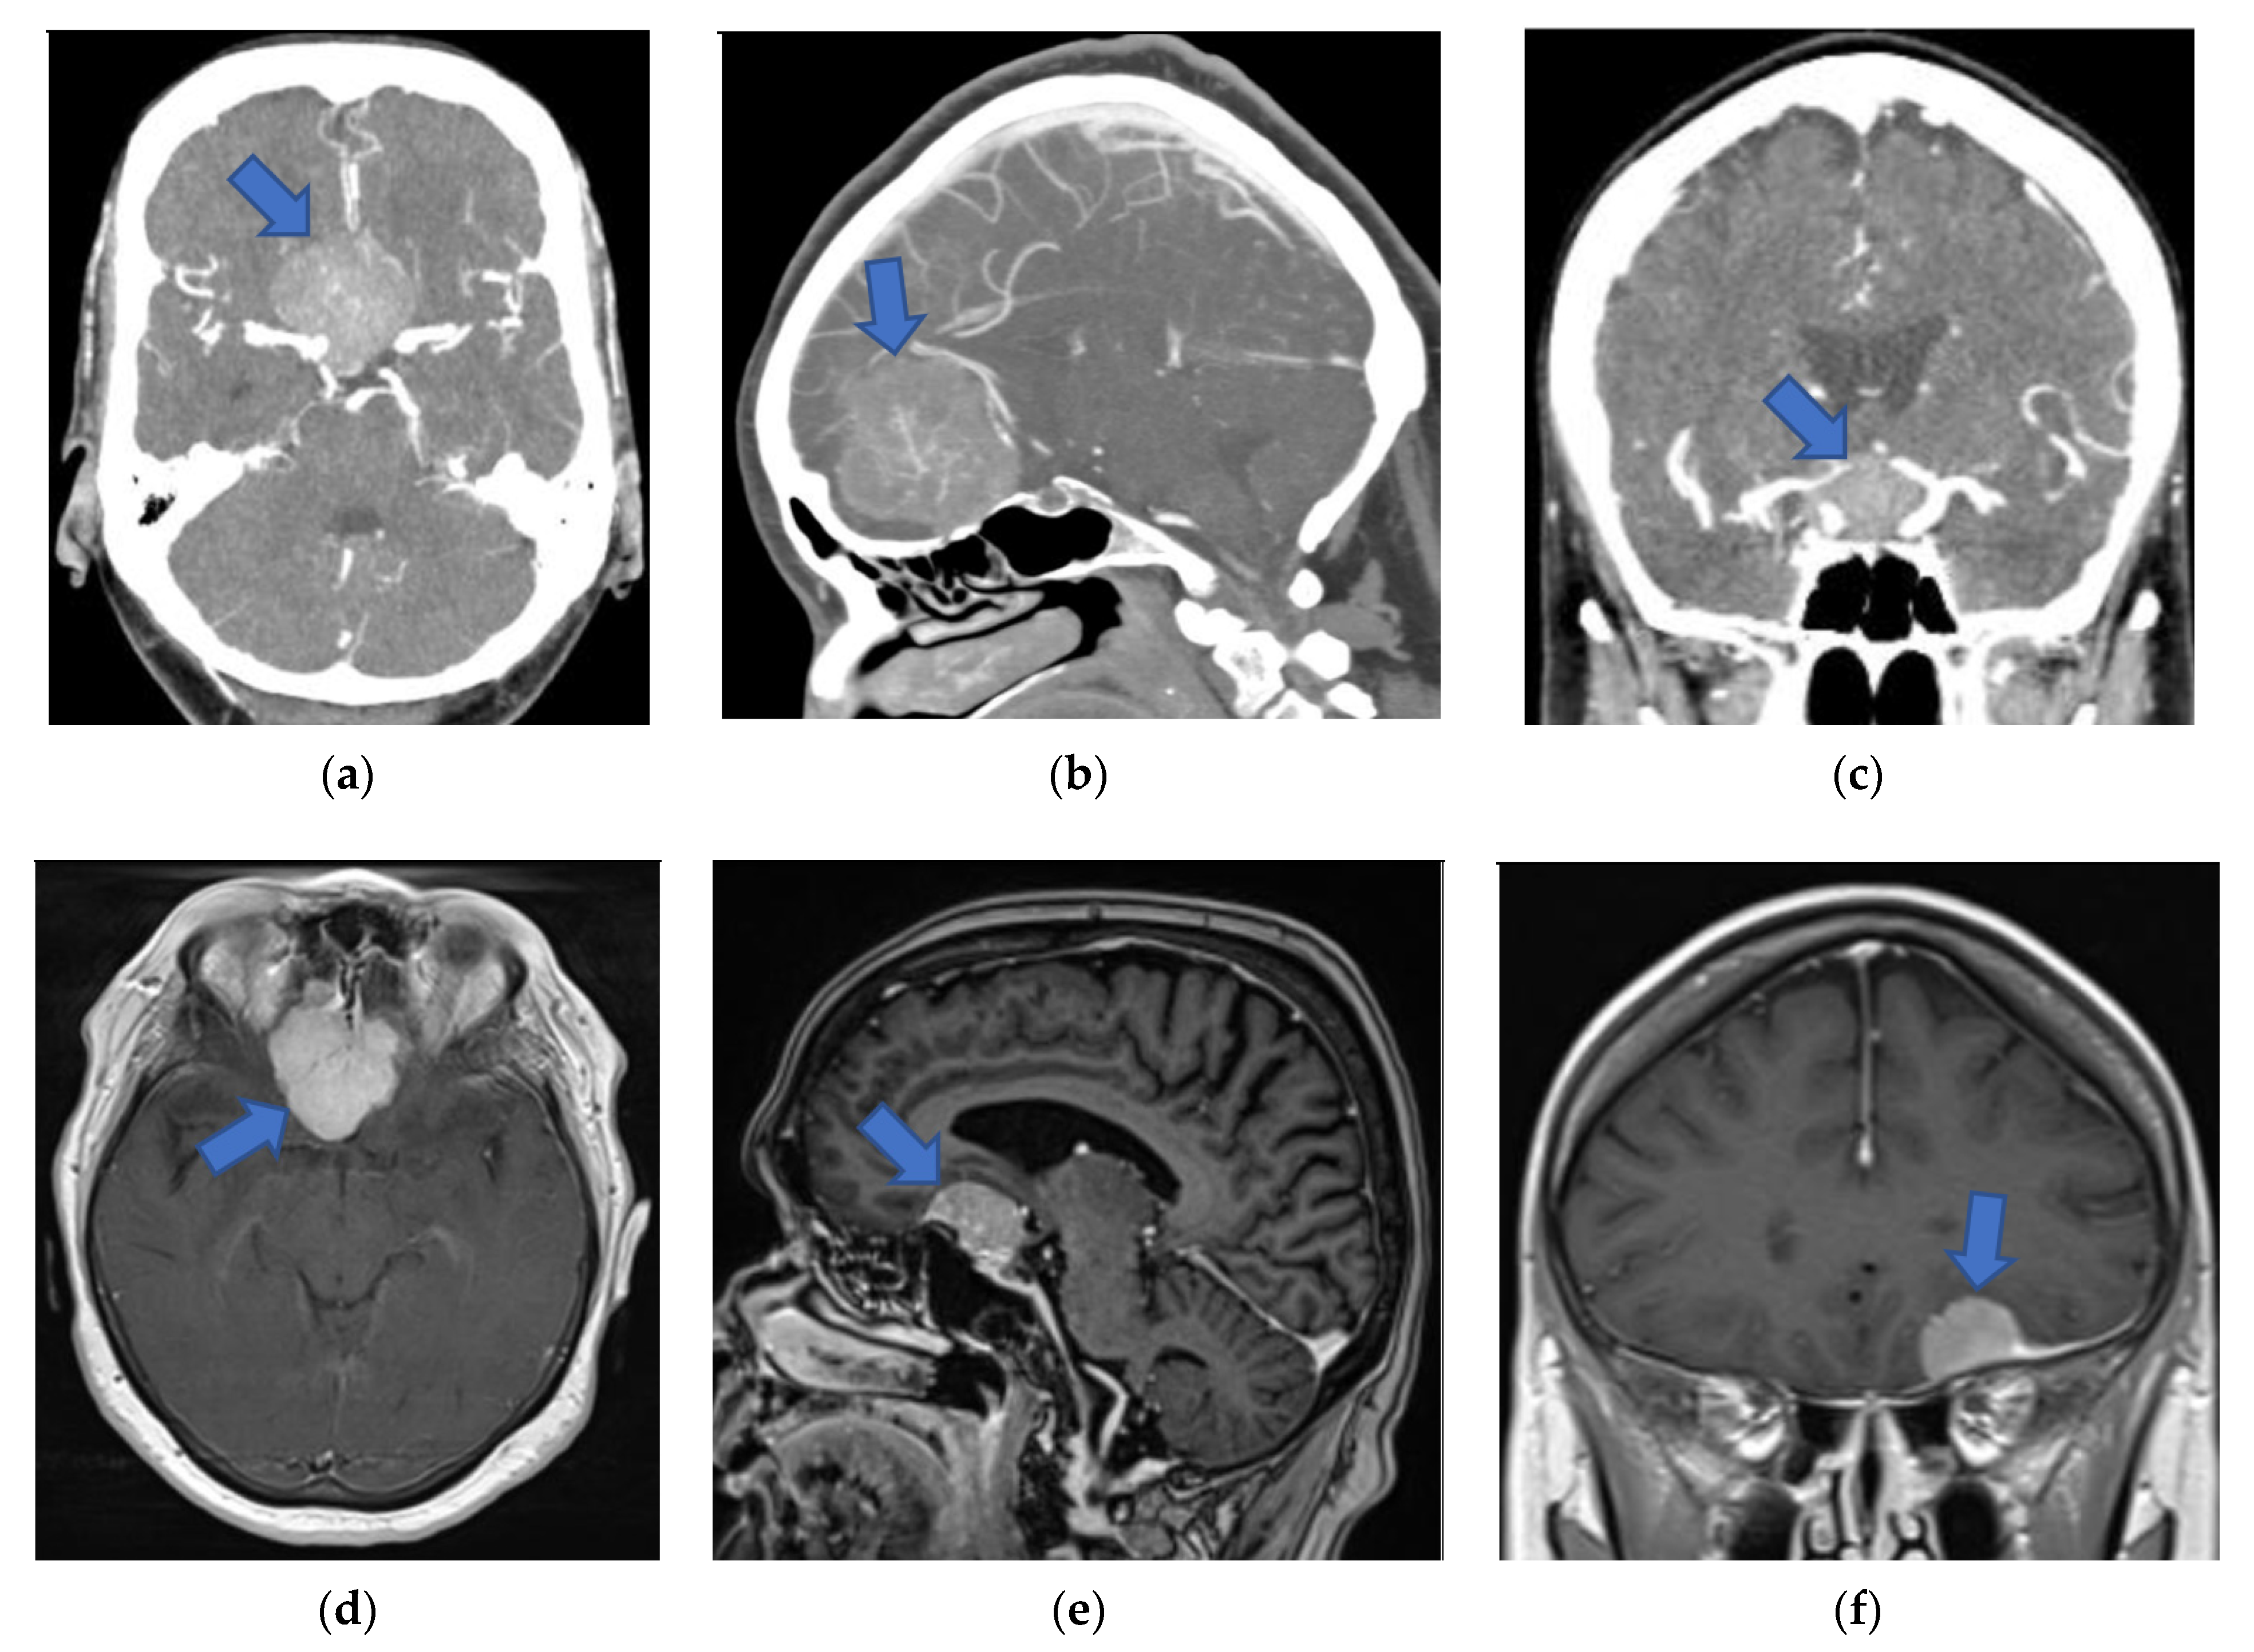

Figure 2. Preoperative 2D and screen 3D images (from CT and MRI modalities) of patients with anterior skull base meningiomas (blue arrows). (a) Axial 2D-CTA image presenting planum sphenoidale meningioma. (b) Sagittal 2D-CTA image presenting olfactory groove meningioma. (c) Coronal 2D-CTA image presenting tuberculum sellae meningioma. (d) Axial 2D-MRI image presenting olfactory groove meningioma. (e) Sagittal 2D-MRI image presenting anterior clinoidal meningioma. (f) Coronal 2D-MRI image presenting frontobasal meningioma. (g) Coronal screen 3D-CT image presenting tuberculum sellae meningioma. (h) Sagittal screen 3D-MRI image presenting olfactory groove meningioma. (i) Sagittal screen 3D-CT image presenting anterior clinoidal meningioma. 2D, two-dimensional; 3D, three-dimensional; CT, computed tomography; CTA, computed tomography angiography; MRI, magnetic resonance imaging.